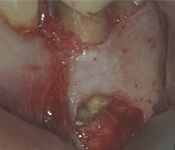

Pictured: Preoperative and Postoperative

Our patient presented with severe pain and required emergency root canal treatment. After cleaning and removing the inflamed pulp, the root canal system was successfully restored and the natural tooth saved.